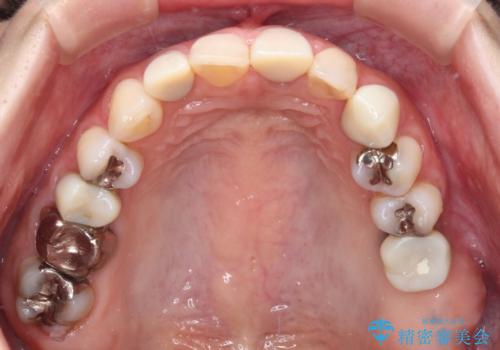

途中通院されなかった時期が何度かあったため、初診から4年以上の年月がかかりましたが、比較的スムーズに治療を進めることができました。

下顎前歯の歯列を整えたことで、上顎前歯の咬み合わせが安定し、自然な口元に仕上げることができました。